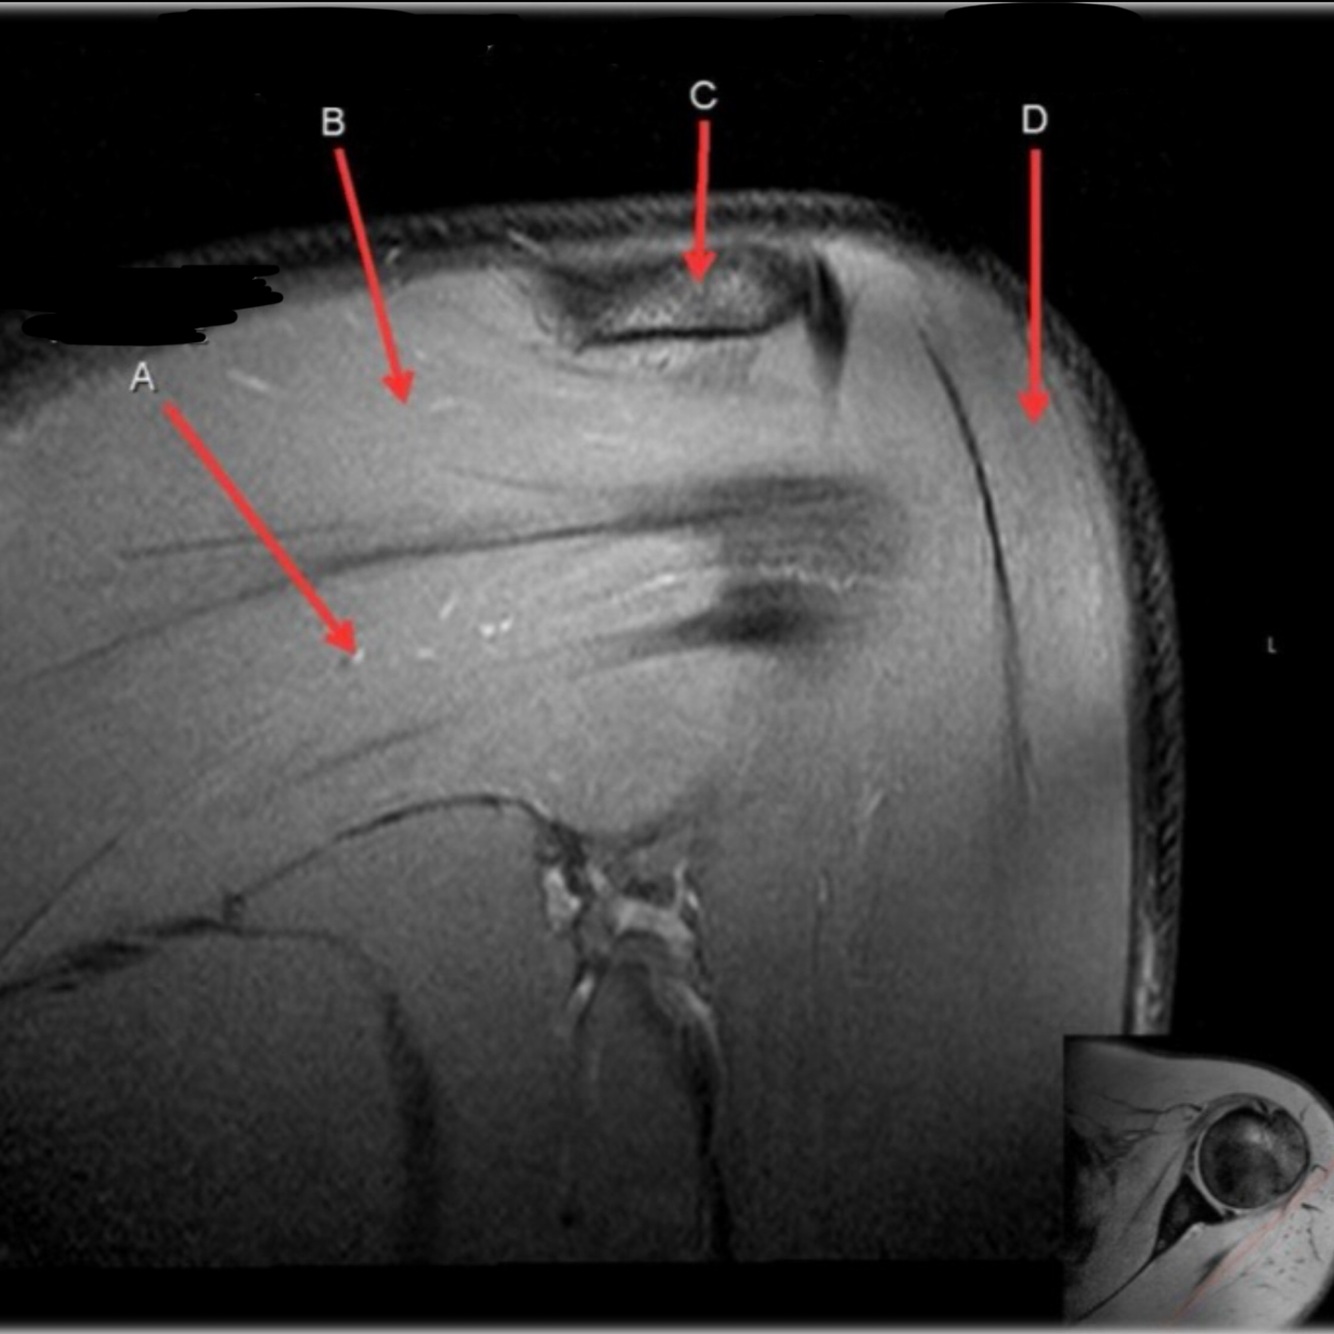

What is letter A?

SUPRASPINATUS TENDON

What is letter B?

ACROMION

What is letter C?

INFRASPINATUS MUSCLE

What is letter D?

SUPRASPINATUS MUSCLE